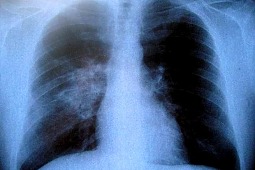

Badania przeprowadzone w Chinach wykazały, że jedzenie surowego czosnku dwa razy w tygodniu może niemal o połowę obniżyć ryzyko zachorowania na raka płuc. Badanie przeprowadzono na grupie dorosłych osób, które czosnek spożywały regularnie. Okazało się, że taka dieta obniżyła ryzyko o 44 proc. Co ciekawe – badanie pokazało, że nawet wśród osób palących papierosy to ryzyko było mniejsze. Jak starają się udowodnić chińscy badacze – aż o 30 proc. Badanie sugeruje, że kluczowym czynnikiem zapobiegającym nowotworom płuc może być zawarta w czosnku allicyna, która działa przeciwzapalnie, jest antyutleniaczem oraz zmniejsza wydzielanie wolnych rodników.